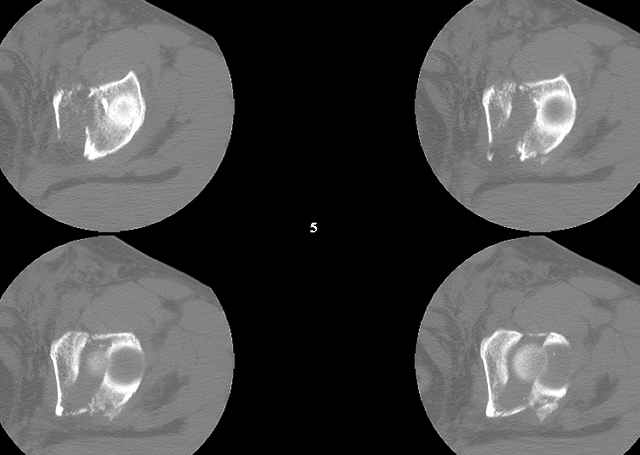

Biggest problem appears to be impaction & comminution of the posterior wall fx site - you've left out some CT cuts. This is not just fragments in joint. It may leave a deficient area, &/or block satisfactory posterior wall reduction.

You can adjust the quadrilateral surface contact point as needed to get the fracture to reduce...we plan this based on the fracture orientation on the preop CT scan images...the clamp should be balanced to avoid over compressing one portion and distracting the other limb. Go back to and you¹ll see on the injury CT where the clamp tines need to be.

A CT scan will rarely lie to you...reveals your reduction and implants...we use it to assess, teach, grade, and try to get better next time.